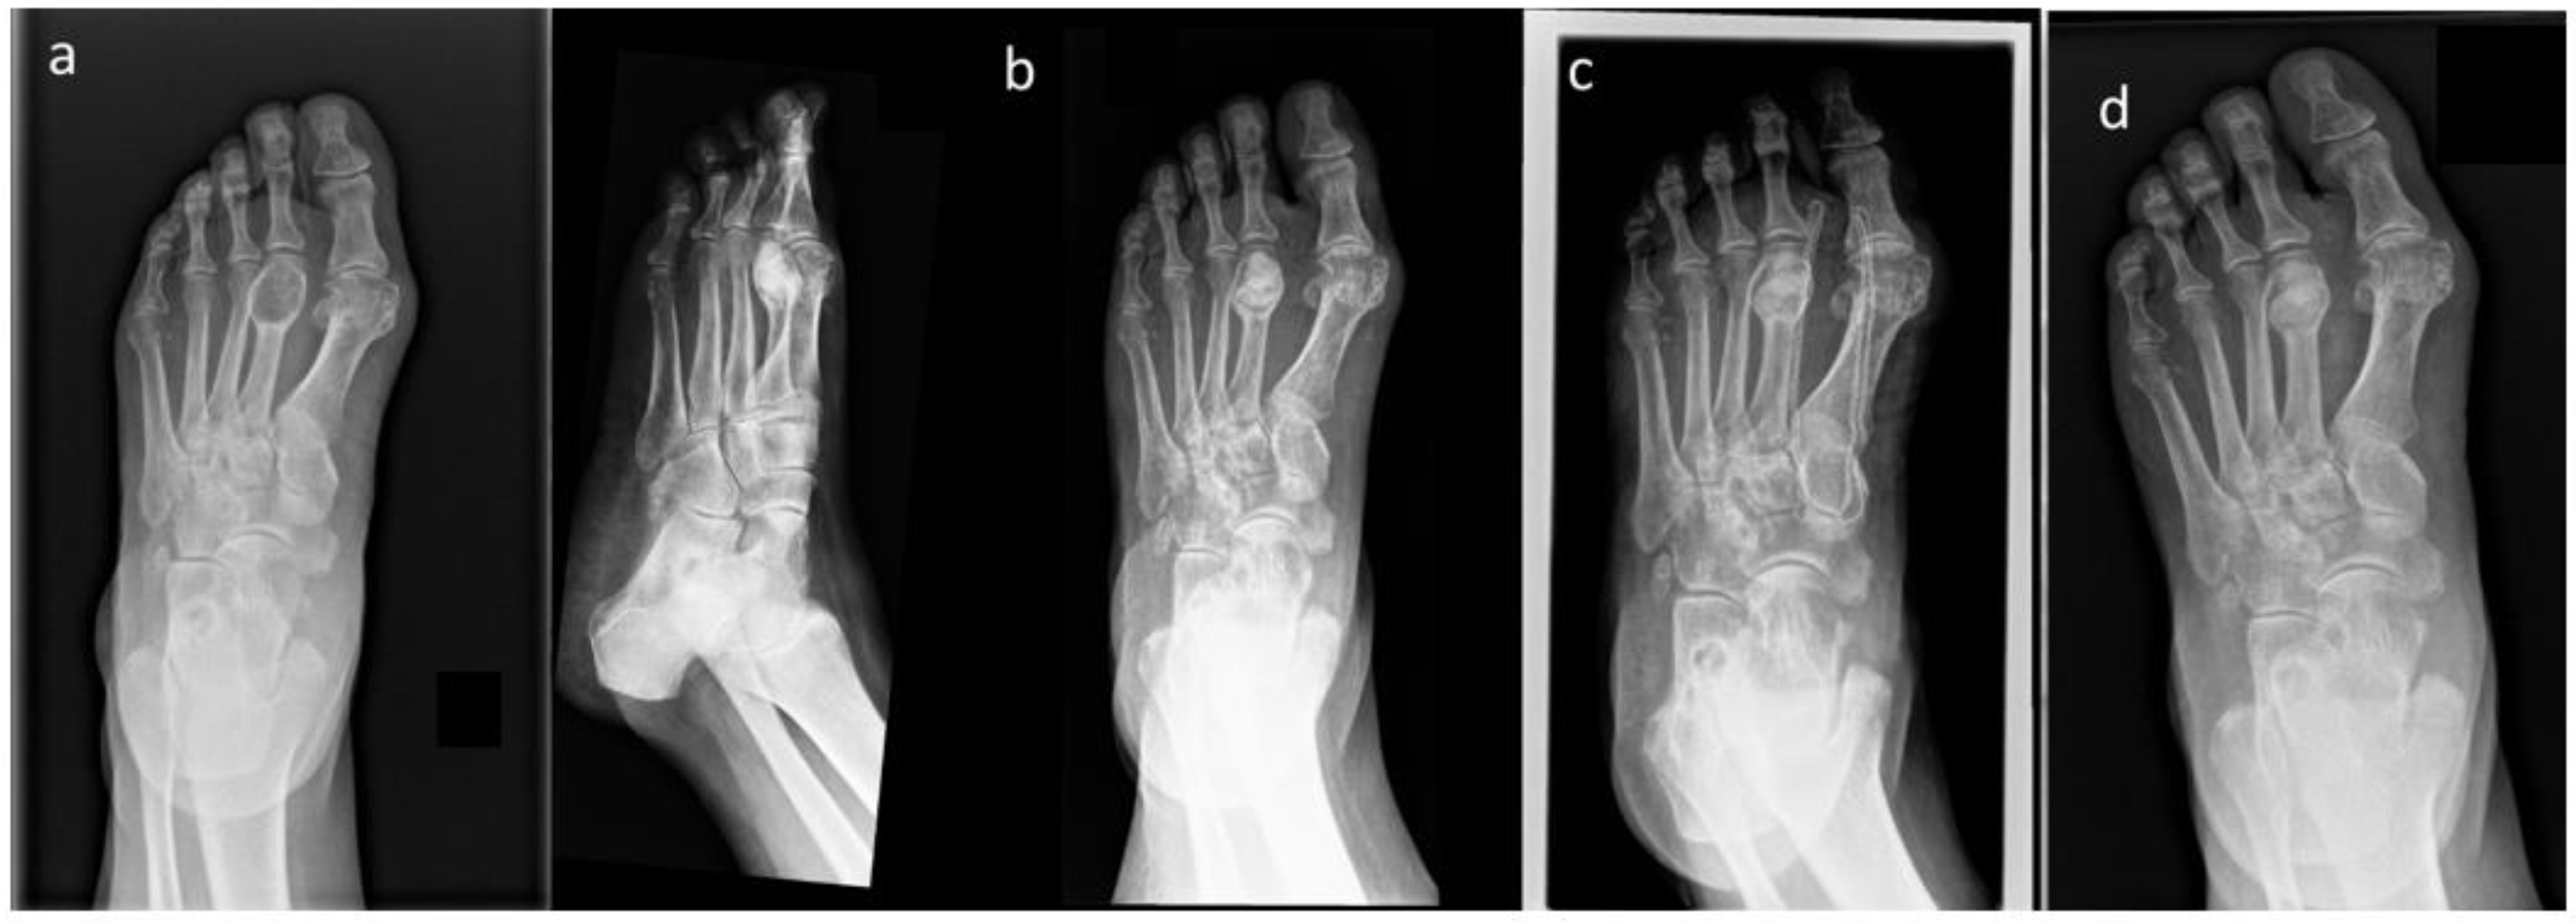

| 2 | F | 66 | Foot (metatarsus) | 30 | Enchodnorma |

| 2 | Score I | 5 | 0 | None |